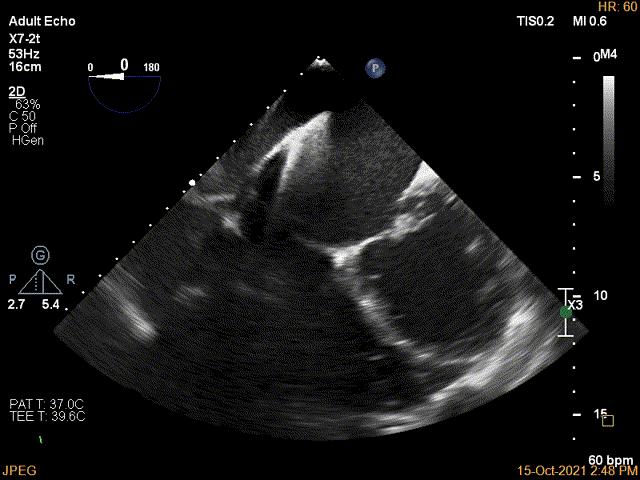

术前超声评估结果

术前超声诊断

3D-color MV view:极大量返流,1、2区均有受累

Qlab软件勾画估测瓣口面积约:6.23cm²